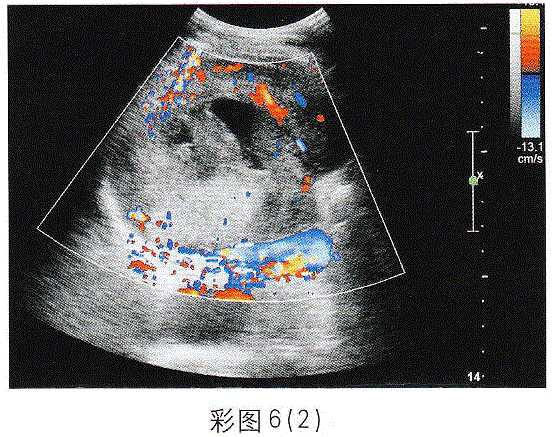

问题 临床资料:男,73岁,自述右上腹压痛伴寒战、高热;无肝炎、肝硬化病史,半年前查体B超显示肝脏未见异常。 超声综合描述: 图1、彩图6(1):肝右叶可见12.2cm×8.3cm不均质回声区,边界尚清,内回声明显不均,由无一低一增强回声,CDFI:周边可见点条状血流信号。 图2、彩图6(2):2周后复查:肝右叶可见10.3cm×8.3cm不均质回声区,内无回声范围较前明显增大,且形态不规则,CDFI:不均质回声区内未见血流信号,周边可见条状血管绕行。 {图2} {图3} 超声提示: